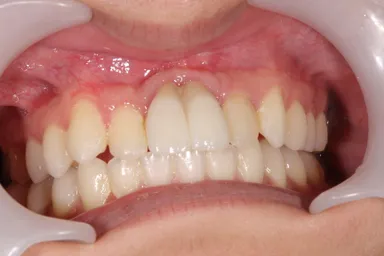

親知らずの移植後

自転車転倒により上の前歯を喪失した患者で入れ歯を入れるも紛失し、インプラント治療以外で治療法がないかと移植に希望をもって当院へ来院されました。当初は下の両側の小臼歯2本を移植し、矯正で抜いた部分を閉鎖しようと検討したものの、矯正医よりスペースの閉鎖は困難と診断され断念。家族、本人の熱意もあり、「埋伏の親知らず」を移植する計画を立て、3D-CTと3Dプリンターを用いての精密なシミュレーションを行った上で施術を行いました。